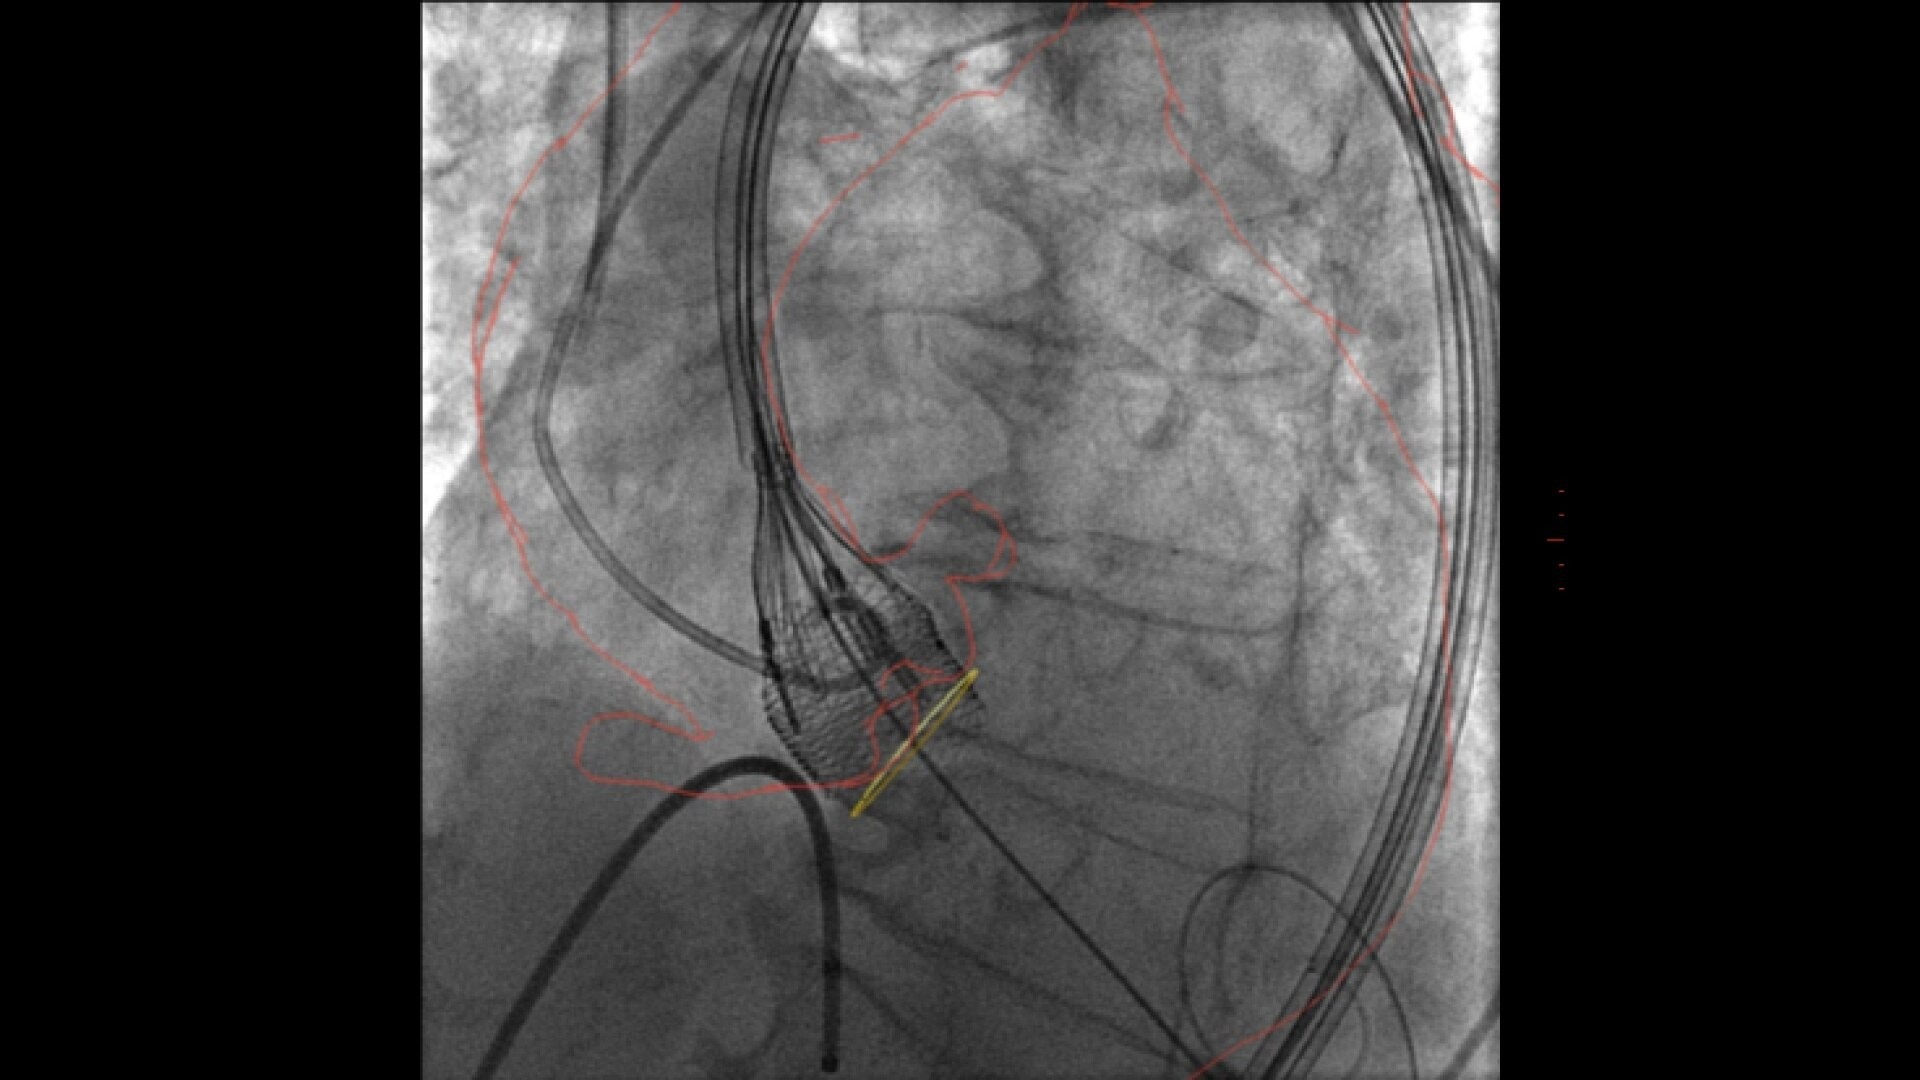

Transcatheter aortic valve implantation

Streamlined workflow for your TAVI procedures

GUIDE

3D fusion guidance enhanced with Calcification Enhancement improves the visualization of moving contrasted structures.

Assess potential regurgitation with exceptional contrast visualization.